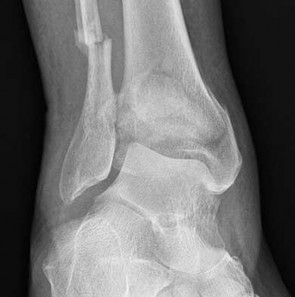

Question 19:

A 35-year-old female sustains a twisting injury to her ankle. Radiographs reveal a transverse fracture of the medial malleolus and a spiral fracture of the proximal third of the fibula (Maisonneuve fracture). For this specific fracture pattern to occur, which of the following ligamentous structures MUST be completely disrupted?

Correct Answer: Syndesmotic ligament complex and interosseous membrane

Explanation:

A Maisonneuve fracture is a pronounced variation of a pronation-external rotation (PER) injury. The mechanism involves external rotation of the talus, which either avulses the medial malleolus or ruptures the deltoid ligament, then disrupts the anterior inferior tibiofibular ligament, tears up the interosseous membrane all the way to the proximal fibula, and exits as a high fibular fracture. Therefore, the syndesmotic complex and the interosseous membrane up to the level of the fracture are intrinsically disrupted.